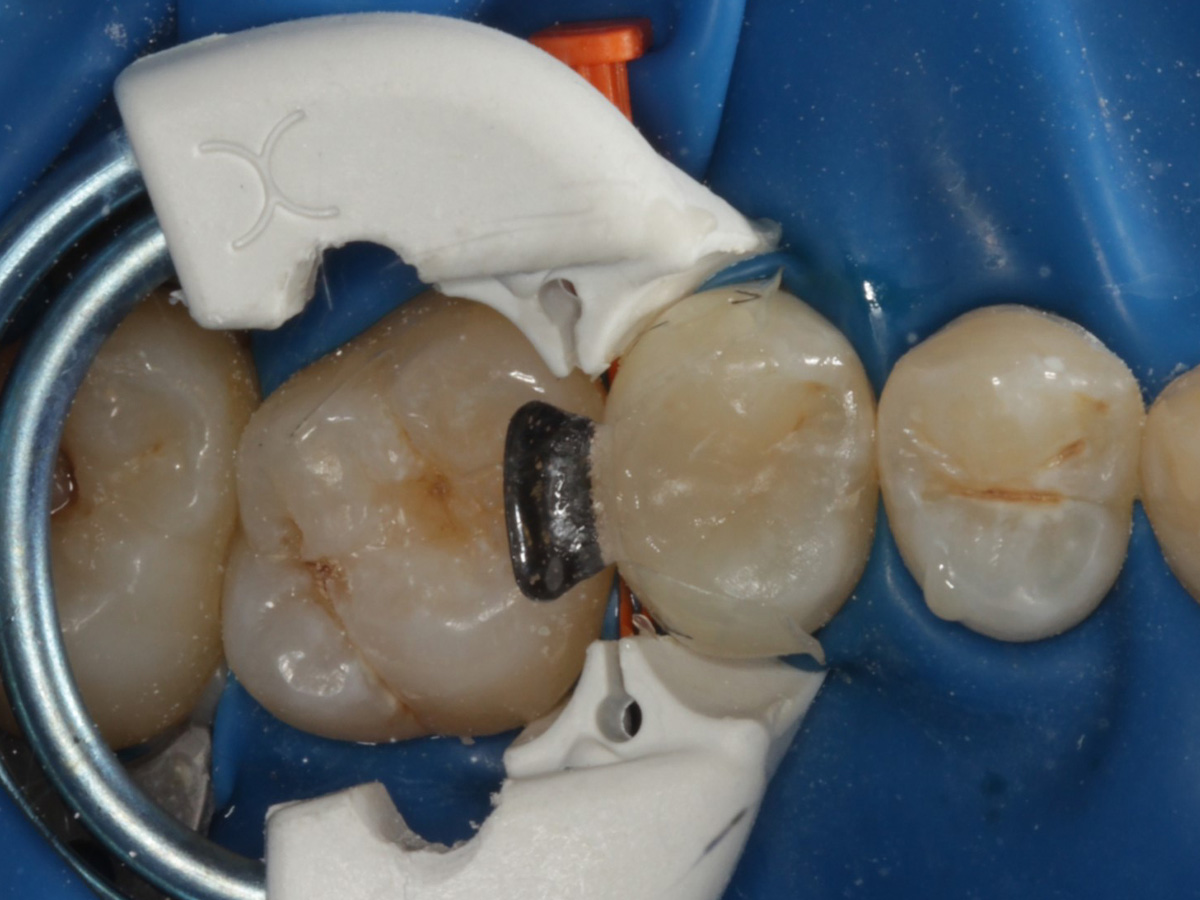

Abbildung 13

Weiteres Flowkomposit appliziert und Bioclear Twin Ring Universal angebracht